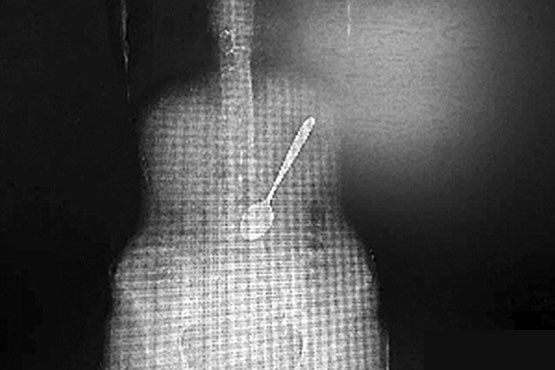

اخیرا در فضای مجازی تصاویری از وجود یک قاشق فلزی بزرگ در معده زنی منتشر شده که در حین خوردن رشته آن را قورت داده بود!.جراحان چینی توانستند با موفقیت یک قاشق 6 اینچی فلزی را از معده یک زن در آورند.

این قاشق فلزی به مدت سه ساعت در شکم بیماری به نام «Wang» ماند و پس از انتقال به بیمارستانی در یانژو در شرق چین بلافاصله تحت عمل جراحی قرار گرفت.

پس از بررسی پزشکان مشخص شد که وضعیت این زن وخیم تر از آن چیزی است که در ابتدا تصور می شد.نتایج سونوگرافی نشان داد که طول این قاشق 6 اینچ است و در دمای 30 درجه سانتی گراد در درون معده این بیمار، هر لحظه احتمال داشت که به روده وی وارد شود که بسیار خطرناک بود و ممکن بود به مرگ «Wang» منجر شود.

پزشکان اعتقاد داشتند که بهترین راه برای خارج کردن قاشق از معده این شخص دهان است که پس از تلاش های بسیار توسط ابزار آندوسکوپی، در طی دو ساعت آن را از معده فرد بیمار خارج کردند.

سختی بیرون کشیدن این قاشق به سبب وجود مقدار زیادی غذای هضم شده در معده فرد و گرد بودن سر قاشق بود که به راحتی قابل بیرون کشیدن نبود.در نهایت عمل جراحی با موفقیت انجام شد و «Wang» توانست به سلامت به خانه باز گردد.